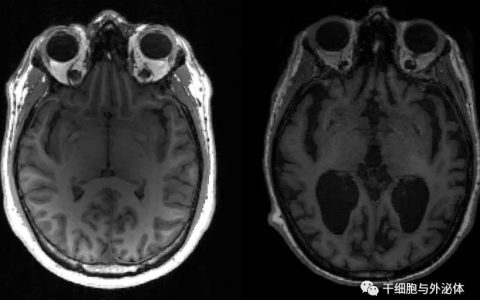

目前,干细胞疗法的基础和临床研究已在全球范围内展开,主要针对糖尿病、肝硬化、白血病、脑卒中、银屑病、脊柱损伤等多种病症,并取得了显著的成效。传统上认为,干细胞疗法是通过细胞分化替代的方式来修复靶器官中的损伤,从而起到治疗的效果。

当前研究证明,间充质干细胞(MSC)来源的外泌体,在减少心肌梗死面积、减轻肢体缺血、增进伤口愈合、改善移植物抗宿主病、减少肾损伤、促进肝再生、减轻视网膜损伤、以及改善软骨和骨再生等方面具有重要作用。

作为纯天然的载体,上文提到外泌体可逃避人体免疫细胞的追击,除此之外,外泌体还有潜力解决神经类药物的一个老大难问题,就是穿越血脑屏障,并且能在极端条件(比如酸,消化酶等)下生存,给实现口服提供了可能性。